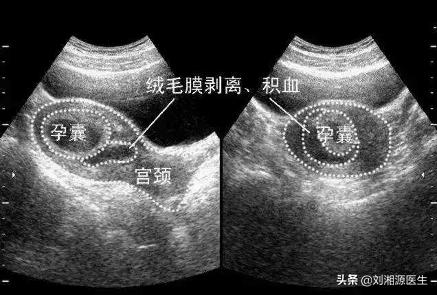

13.如何发现绒毛膜下血肿?

答:1)超声检查:这是常规诊断技术,通过超声可发现低回声或无回声的液性暗区包绕着部分妊娠囊,表面不规则,常呈月牙形,三角形及环形,可进入胎盘后面。

2)磁共振检查:必要时,孕18周后可进行,较超声检查更能清晰显示血肿部位及范围,但临床很少用。。

14.超声如何鉴别绒毛膜下血肿发生出血的时间?

答:1)血肿回声高于妊娠囊壁或叶状绒毛膜:提示发生在48h内(急性期);

2)血肿回声近似于妊娠囊壁或叶状绒毛膜,血肿内回声较如纤维条带样、团块状等: 提示发生在3~7d(亚急性期);

3)血肿呈低或无回声:提示发生超过7天(慢性期)。